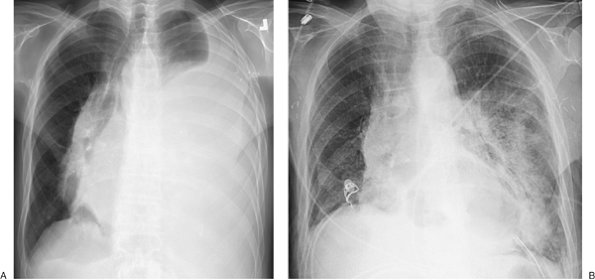

FIGURE 9-12. Re-expansion pulmonary edema. A: PA chest radiograph of a 78-year-old woman with metastatic breast cancer shows a large left pleural effusion associated with collapse of the left lung and shift of the mediastinum to the right. These findings suggest tension hydrothorax. B: PA chest radiograph after placement of a left chest tube and adequate drainage of pleural fluid shows re-expansion pulmonary edema on the left.